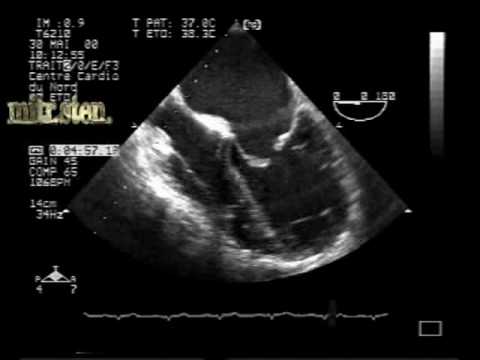

MS Different Aspects:mitral Stenosis TEE - YouTube

MS different aspects:mitral stenosis TEE - YouTube www.youtube.com

mitral stenosis tee valve ms